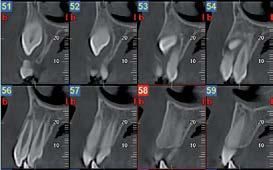

Nell’ambito della radiologia 3D ortopedica, il centro diagnostico utilizza il nuovissimo macchinario NewTom 5G XL, in grado di individuare con la massima precisione la presenza di fratture o lussazioni delle articolazioni, controllare la corretta guarigione di una frattura, valutare una lesione o una ferita causata da infezione, artrite o crescita anormale dell’osso.

Il tutto mediante una semplice e veloce scansione, grazie alla quale si otterranno diverse immagini in 3D ad altissima risoluzione e, per ottenere immagini ancora più nitide mediante un bassissimo dosaggio di radiazioni, gli esperti si avvalgono dell’innovazione racchiusa nella tecnologia Cone Beam.

Se con la radiologia tradizionale era necessario eseguire scansioni multiple, la novità introdotta dal macchinario NewTom 5G XL risiede nella capacità di fornire immagini ad alta risoluzione in un’unica scansione, mostrando nitidamente i dettagli delle articolazioni degli arti superiori e inferiori. Inoltre, a differenza della tecnologia 2D, la radiologia 3D ortopedica permette di individuare immediatamente alcune patologie come quella del metatarso, la quale richiede un allineamento visivo dedicato o una diagnosi delle micro fratture ossee.